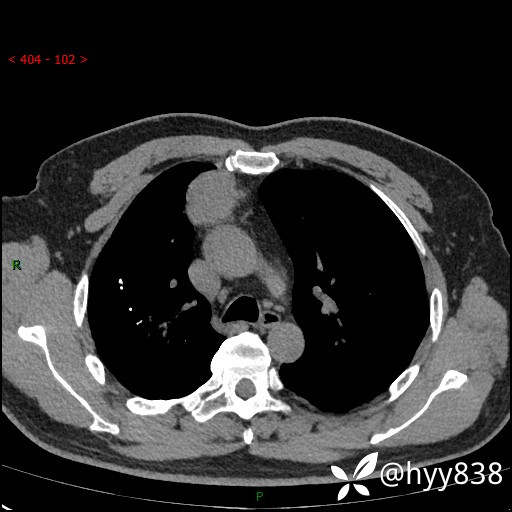

胸部CT平扫